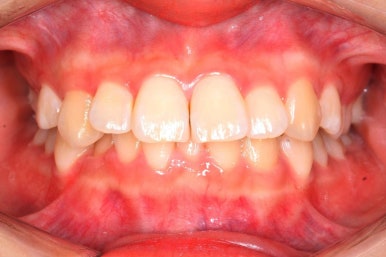

몇 달간의 마무리과정을 거치고 드디어 장치를 제거하였습니다.

위아래 앞니는 다시 틀어지지 말라고 유지철사를 붙였습니다.

위에는 탈착이 가능한 유지장치도 사용합니다. 2중으로 안전장치를 하는 것이죠.

치아는 매우 가지런해졌고, 과개교합도 개선이 되었으며 뻐드러진 앞니 각도도 정상적으로 회복이 되었습니다.

치아가 가지런해졌습니다.

뻐드러진 앞니가 정상적인 각도로 회복되었습니다.

전반적인 치아들의 위치가 뒤로 이동하였습니다.